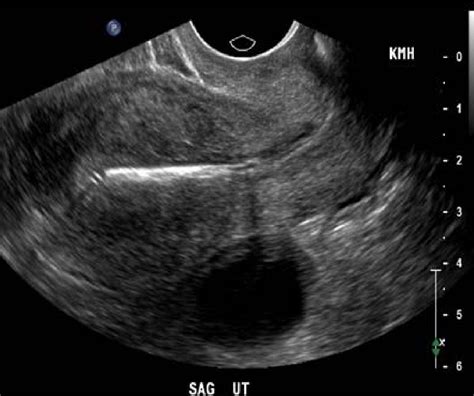

To truly grasp how effective are IUDs, it is helpful to understand how they work within the body. An IUD is a tiny, T-shaped device made of flexible plastic that is inserted into the uterus by a healthcare provider. There are two primary categories of IUDs: hormonal and copper-based. Both types serve as highly effective barriers to pregnancy by altering the uterine environment.